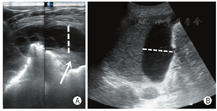

(1)将探头置于BLUE-PLUS方案确定的5个标准位点的肋间,然后于各位点进行横向(探头平行于肋间隙,图3A)和纵向扫查(探头垂直于肋间隙,图3B)。进行PLAPS点的扫查时探头方向指向前胸胸骨方向为宜。同时可以对照患者CT所提示病变区域所在体表投影区域对应扫查,标记并存图。

横向扫查时,显示光滑胸膜线,至少显示2条水平方向的A线;纵向扫查时表现为"蝙蝠征"(两侧肋骨声影与之间胸膜线构成)。正常肺部图像应显示胸膜线、A线,能够观察到肺滑动征(图4)。

胸膜线:胸膜与肺表面界面声阻抗差异形成的回声反射,呈光滑、清晰、规则的线性高回声。

A线:胸膜与肺界面声阻抗的差异产生多重反射而形成的伪像,位于胸膜线下方,呈一系列与之平行的光滑、清晰、规则的线性高回声,彼此间距相等,回声由浅入深逐渐减弱至消失。

肺滑动征:实时超声下可见脏层胸膜与壁层胸膜随呼吸运动而产生一种水平方向的相对滑动。